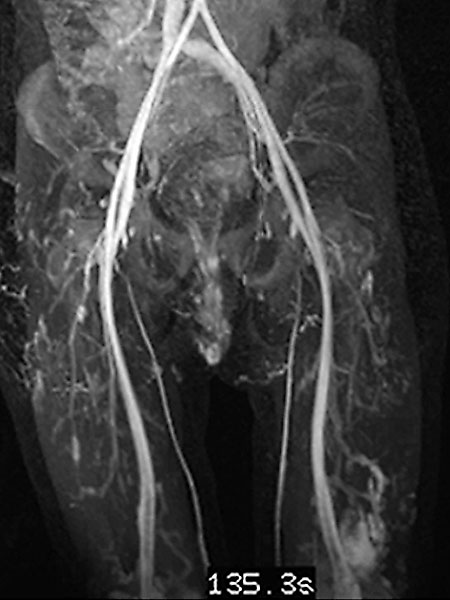

In the late phase of dynamic, high temporal resolution, contrast-enhanced MR angiography 135 seconds after i.v. contrast administration, there is slow, delayed contrast pooling in the lesion. Thus, an arteriovenous malformation with its rapid flow can be clearly excluded. Additional slow contrast pooling of the second lesion on the lateral distal left thigh.